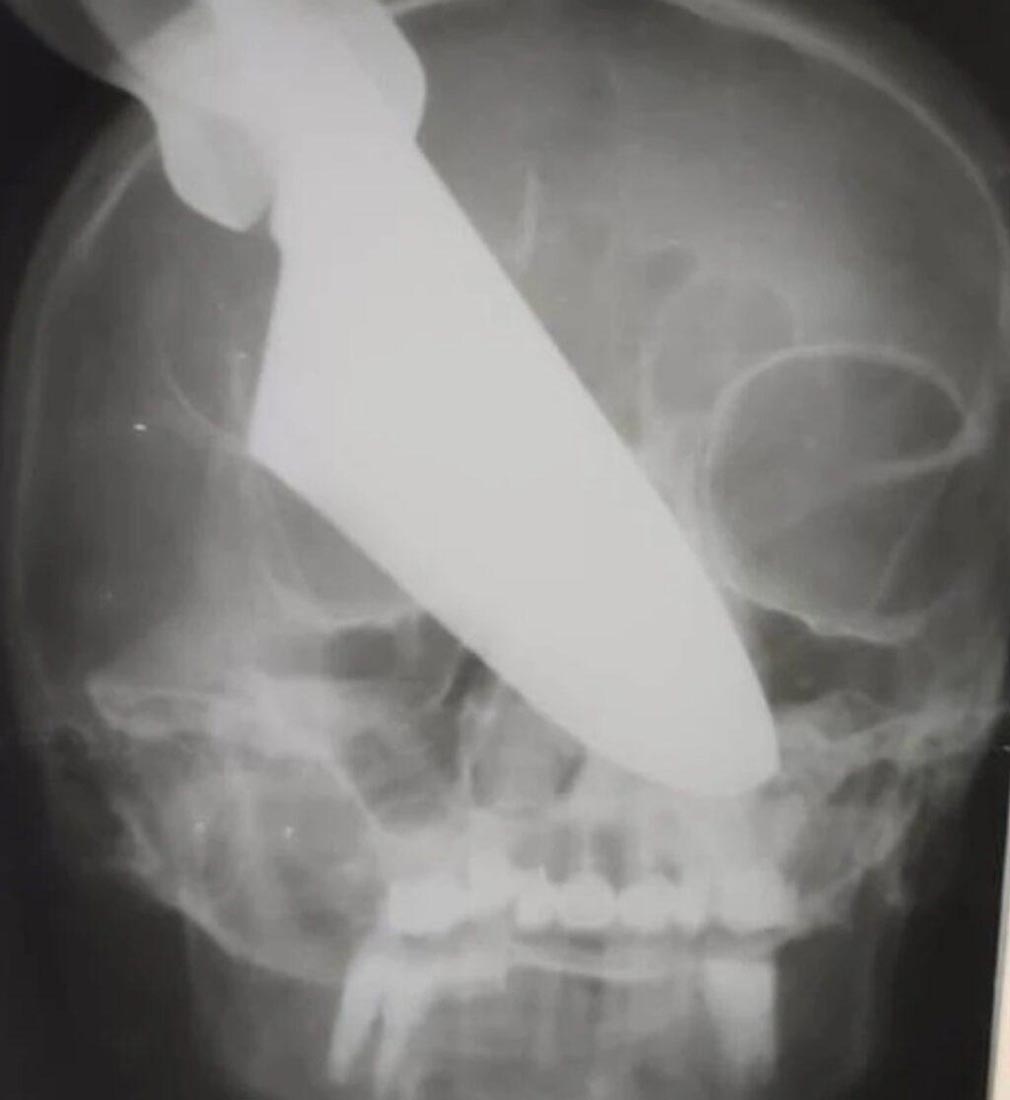

Sarhoş koca dehşeti! Rusya'da sarhoş koca tartıştığı sırada eşinin gözüne büyük bir bıçak sapladı. Hastaneye kaldırılan kadının gözünü kaybettiği belirtilirken bıçağın kadının gözünden 25 santimetre içeri girdiği belirtildi.

Bilinci yerinde olan kadın ameliyata alındı. Doktorların uzun uğraşları sonucu kadının gözüne saplanan bıçak çıkarıldı. Bıçağın kadının gözünden 25 santimetre içeri girdiği belirtildi. Talihsiz kadın bıçağın saplandığı gözünü kaybetti.